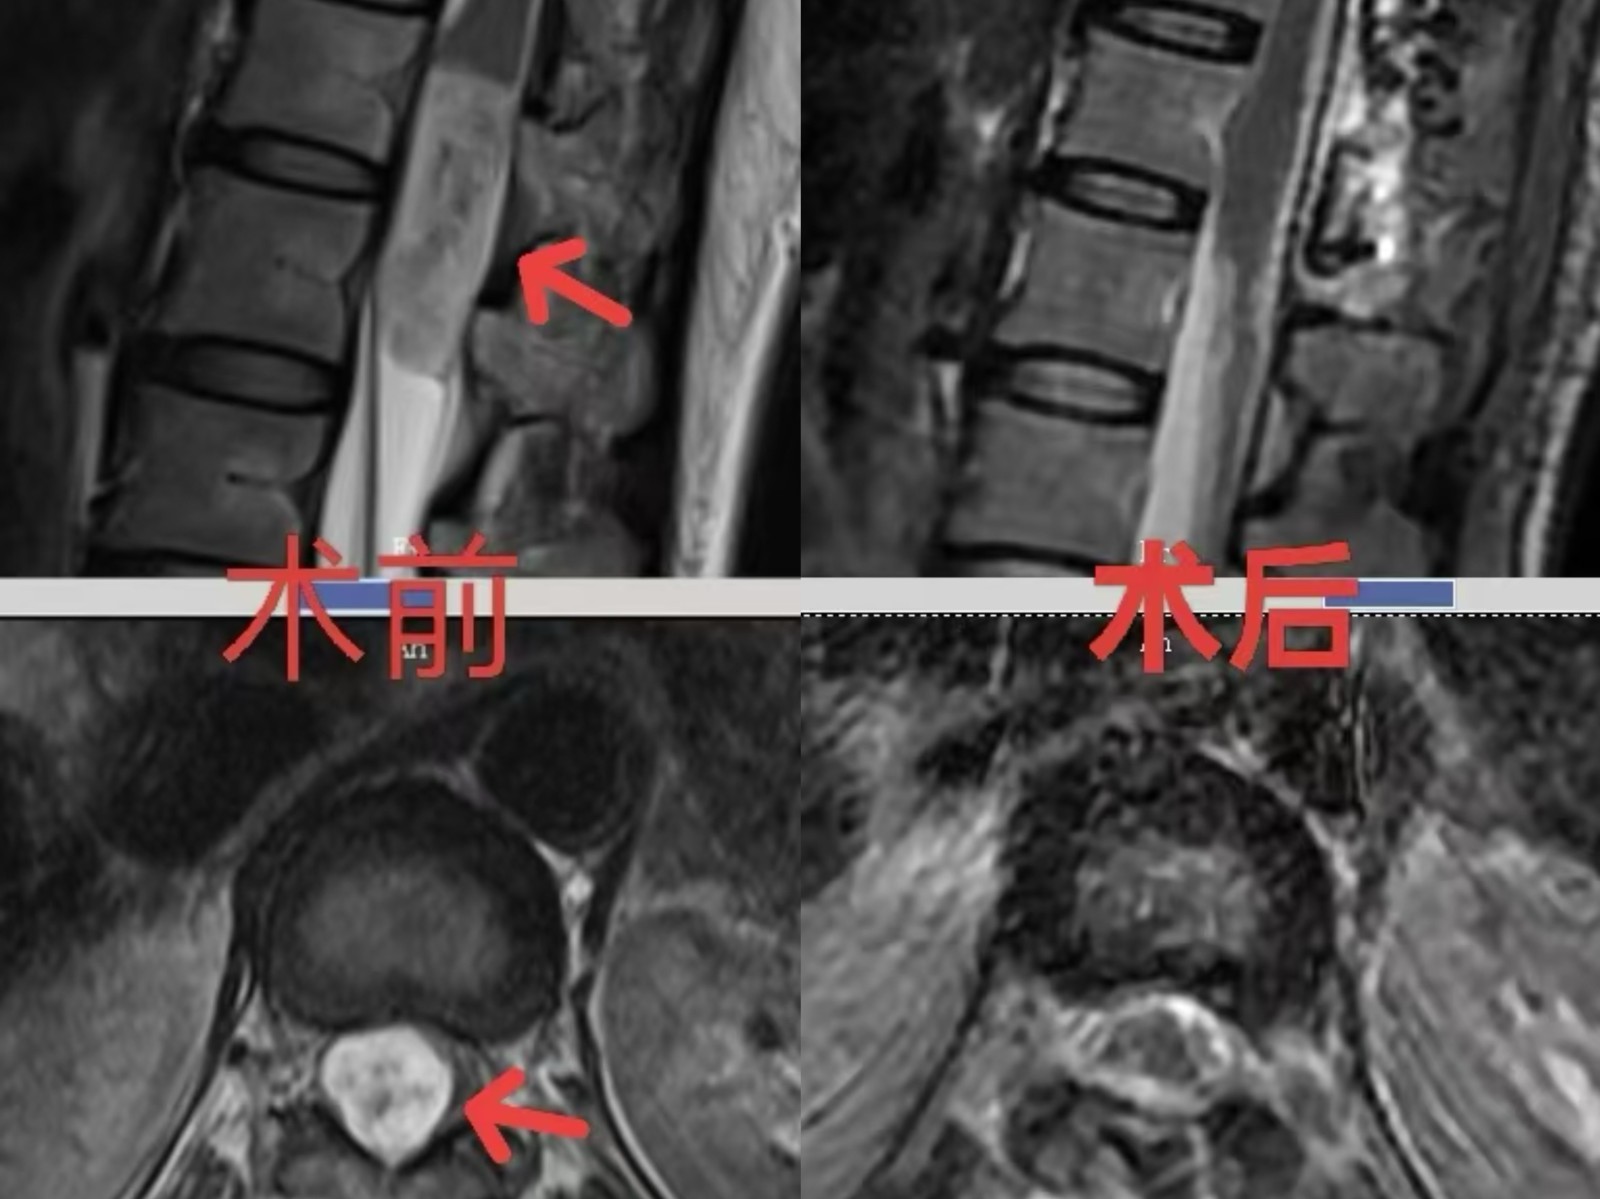

脊髓结构最粗的地方仅仅像我们的手指,该肿瘤大小约4厘米*1.5厘米,已经接近正常结构大小,脊髓圆锥受压严重,被压成了一个薄薄的片状。肿瘤深藏腰椎椎管内,被脊髓、神经根、紧密包绕。手术犹如在神经与血管的“雷区”中拆弹,稍有不慎即可导致不可逆的损伤,对手术团队技术要求极高。

经周密术前准备,神经外科二病区罗俊杰主任团队为曹女士实施了椎管肿瘤切除术。术中发现肿瘤与圆锥处粘连严重。在显微镜下,靠着医生的耐心与精湛的技术,一点一点地将肿瘤分离,手术历时5个多小时,最终将肿瘤全切,并且正常结构得以完全保护。